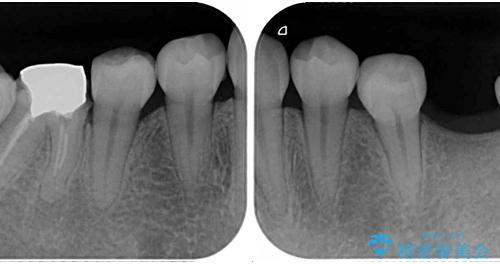

- 放置した虫歯や抜いたままの奥歯、前歯のデコボコを気にして来院された患者様です。

口元の突出感は少なく、下顎の叢生は軽微なものであったので、叢生の強い上顎左右の小臼歯を1本ずつ抜歯し、ワイヤー装置にて矯正治療を行うこととしました。

矯正治療を行う前に、根管治療の必要な上顎前歯と下顎大臼歯の根管治療を行い、矯正治療の途中で下顎の欠損部にインプラント埋入することとし、矯正治療後に補綴治療を行うこととしました。